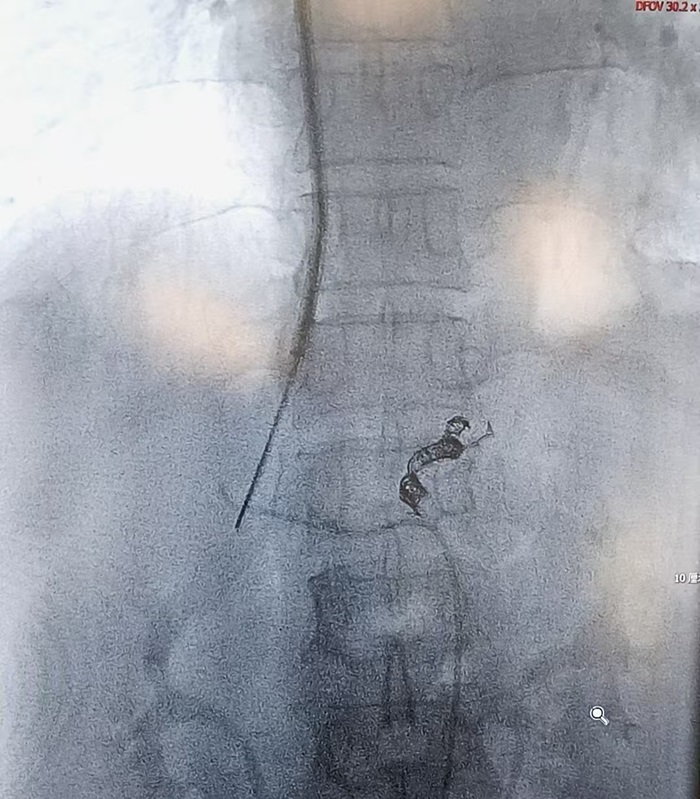

实施皮肝穿刺胃食管曲张静脉栓塞硬化术